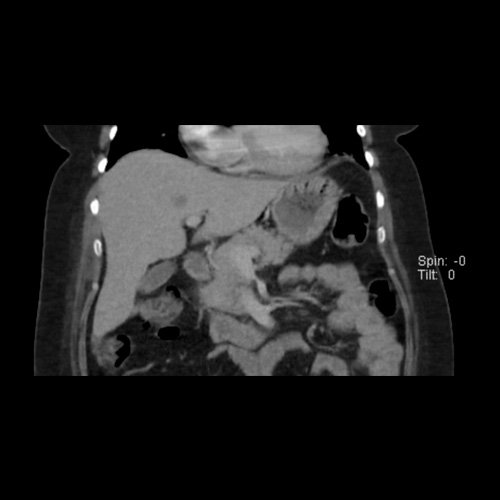

Tomografía de abdomen y pelvis sin contraste oral con contraste EV (12/02/26): El hígado es de forma, tamaño y situación habituales. Su superficie es lisa, y sus bordes son agudos. Imagen hipovascular aislada de 15 mm en segmento V de aspecto inespecífico. Sugiero complementar con RMI. La vía biliar intra y extrahepática es de calibre conservado. La vesícula biliar es de forma, tamaño y situación normales, sin imágenes que sugieran la presencia de litiasis. Tener en cuenta que este método puede pasar por alto litiasis colesterínicas. El bazo es de forma, tamaño y situación normales. El páncreas es de características normales. El conducto de Wirsung es de calibre conservado. Adenoma adrenal izquierdo de 16 mm. Ambos riñones son de forma, tamaño y situación habituales. Concentran y eliminan adecuadamente la sustancia de contraste. Sin evidencia de alteraciones calicopiélicas ni ureterales. La aorta, las arterias ilíacas primitivas, internas, externas y femorales, son de calibre y trayecto conservado, permeables. La vena cava inferior y las venas ilíacas primitivas, internas, externas y femorales son de calibre y trayectoria conservados, permeables. No se observan adenomegalias intraperitoneales, retroperitoneales, ilíacas ni inguinales. No se observan alteraciones a nivel del tracto gastrointestinal. La vejiga es de paredes lisas, sin presentar efectos de masa endoluminales ni parietales. Utero en AVF, lateralizado a izquierda. Pequeña hernia umbilical de contenido graso y escaso líquido intrasacro. No se identifican alteraciones en las estructuras óseas visualizadas.

TC de abdomen y pelvis con contraste endovenoso (12/02/2026) Corte axial: hígado de forma, tamaño y situación habituales, con superficie lisa y bordes agudos. Imagen hipovascular aislada de 15 mm en segmento V de aspecto inespecífico.

TC de abdomen y pelvis con contraste endovenoso (12/02/2026) Corte coronal: hígado de forma, tamaño y situación habituales, con superficie lisa y bordes agudos. Imagen hipovascular aislada de 15 mm en segmento V de aspecto inespecífico.

TC de abdomen y pelvis con contraste endovenoso (12/02/2026) Corte sagital: hígado de forma, tamaño y situación habituales, con superficie lisa y bordes agudos. Imagen hipovascular aislada de 15 mm en segmento V de aspecto inespecífico.